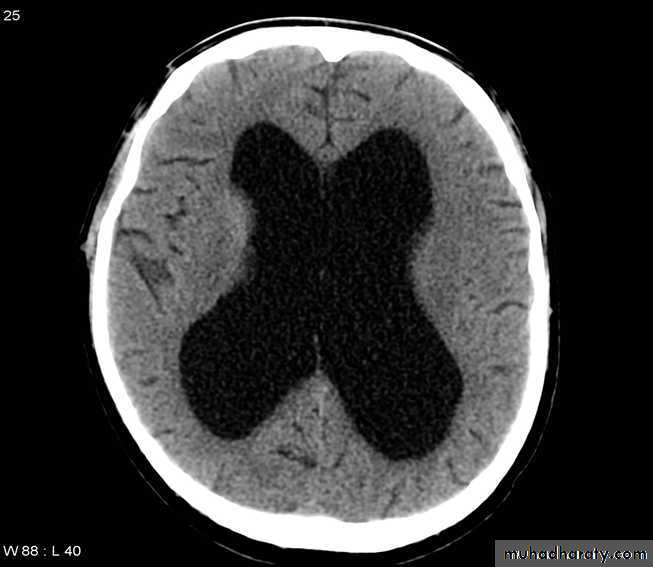

Hydrocephalous

2 types

Obstructive ( non – communicating )

Craniophyrengioma

Medulloblastoma

Ependymoma

Aquiduct stenosis , comments cause of obstruction being congenital in nature .

Non –obstructive ( communicating )

No obstruction of the ventricular pathway , but the absorption of the csf at the level of arachnoids' granulation is occluded secondary to lodge by blood clot or inflammatory cell or infection post meningitis most commonly to occur post SAH .